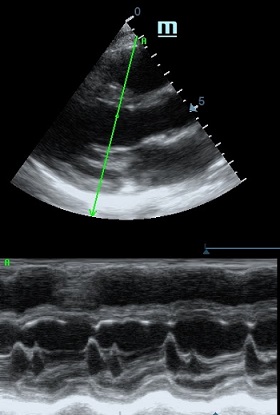

Но как же провести стандартные измерения в М-режиме, если мы его не использовали? На помощь приходит функция Free Xros M – анатомический М-режим. Имея записанную в память прибора видео петлю, мы можем провести линию М-режима в любом месте, при этом корректируя изначально не оптимальный угол.

Оценка кооптации нижней полой вены ещё никогда не была такой простой и точной, никаких лишних деталей, просто устанавливаем клипер по анэхогенному участку.